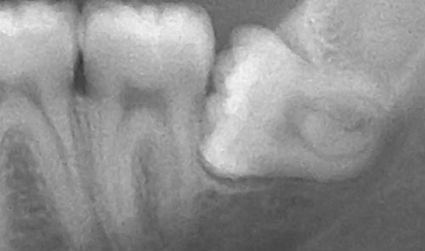

Son ambas una radiografía?

si tuviese el diente torció el pescao iría al dentista o al veterinario?

esta el pez tan descolocado en la foto como esa muela?

Tiene muelas del juicio?

Hay q estirpar la muela del juicio al pez?

Tiene caries?